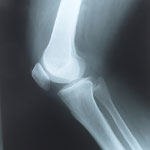

שלום רב בברך ישנם שני מניסקוסים, אחד פנימי(מדיאלי ) ואחד חיצוני (לטרלי), תפקידו של המניסקוס בברך הוא בין השאר לשמש כבולם זעזועים, קרע במניסקוס יכול להפריע לתפקוד התקין של המפרק, קרע במניסקוס יכול לגדול , יכול ליצור נעילות של הברך, כמו כן יכול ליצור פגיעה בסחוס של הברך, כל הדברים שציינתי יכולים להיות אך לא חייבים להיות ,באם מוציאים חלק מבולם הזעזועים של הברך דהיינו המניסקוס עומסים רבים יותר מופעלים על הסחוס . קרעים במניסקוסים לרוב לא יכולים להתאחות ברגע שישנו קרע בחלק מהמניסקוס נוזל הברך יכול להיכנס בקרע וליצור צסטה מנסיאלית , טיפולים כאמור נקבעים על סמך בדיקה גופנית ועיון בבדיקות ההדמיה , אך לרוב באם הטיפול שמרני לא עוזר ישנו גם אופציה של ארתרוסקופיה בברכה ד"ר בנימין בנדר www.DrBender.co.il